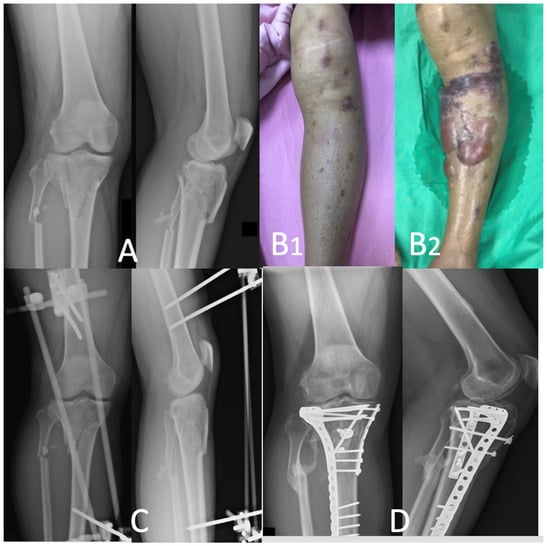

2.2. Surgical Procedures